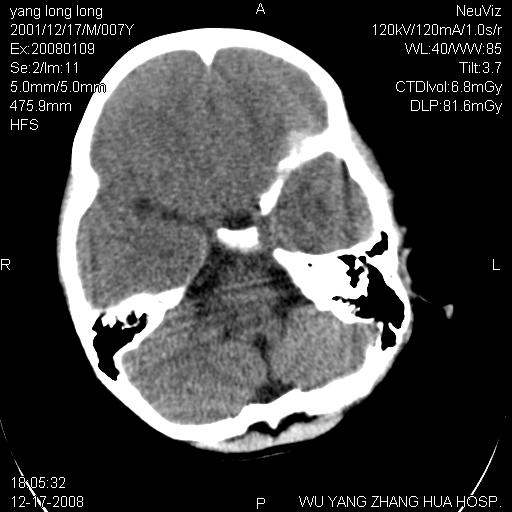

标题: PED1686:M7Y,头外伤,家人及自诉平时无任何不适。 [打印本页]

标题: PED1686:M7Y,头外伤,家人及自诉平时无任何不适。

考虑蛛网膜囊肿,请老师们看看多指导指导。

多考虑大枕大池。本例颅骨歪歪的,灶后枕骨似有膨胀征像(为蛛网膜囊肿征像),但整个左侧枕叶后方枕骨均有向后膨隆,所以暂不考虑蛛网膜囊肿。必要时随访

病变向两侧延伸,颅骨内板受压侵蚀,似有张力!!还是考虑蛛网膜囊肿!!